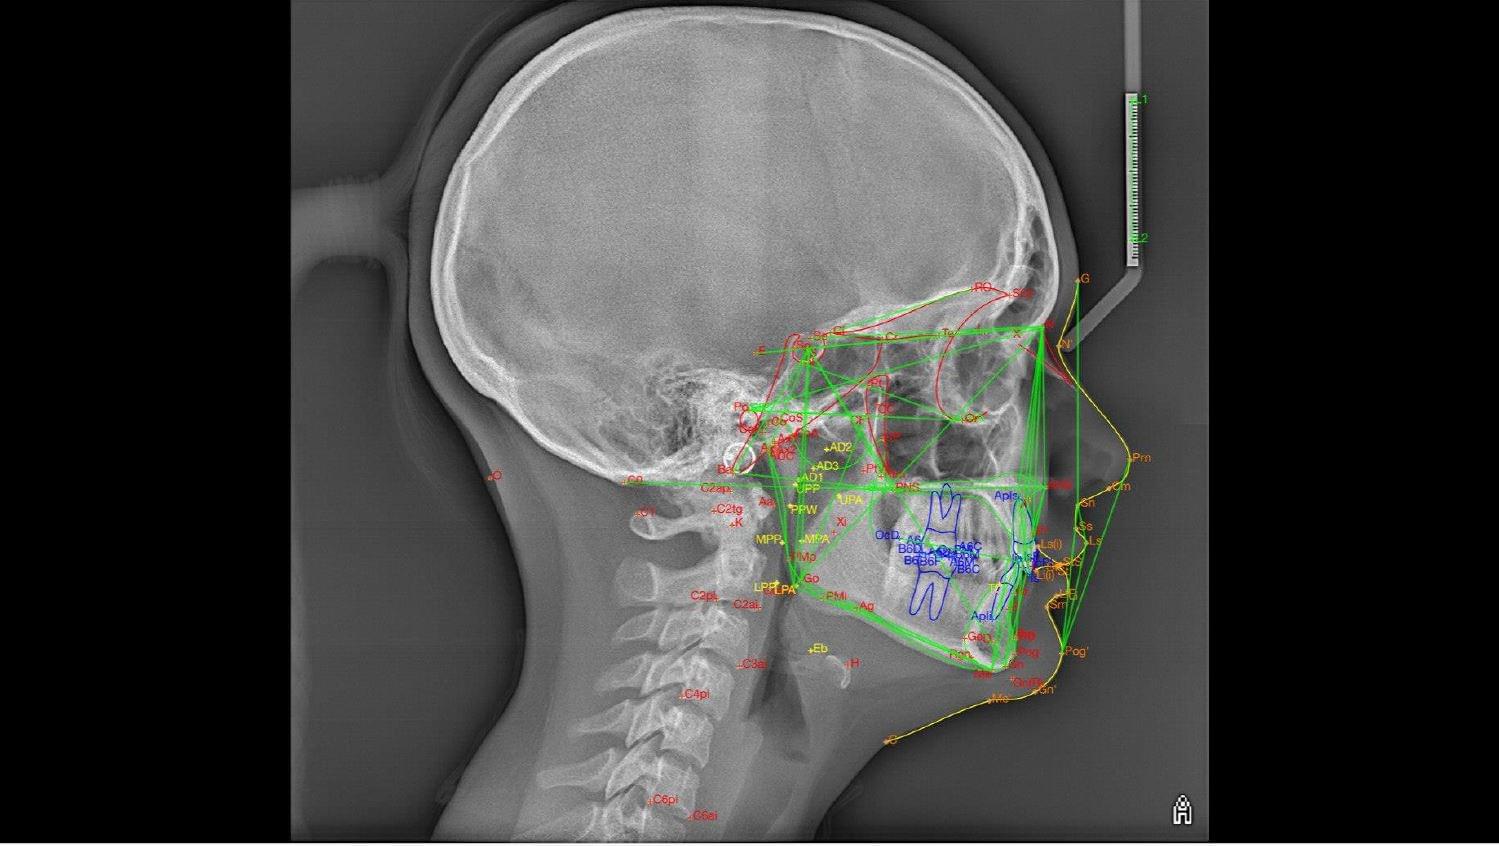

Це окрема діагностична послуга, під час якої лікар-діагност оцифровує знімок, розставляє анатомічні точки та вимірює кути і відстані між кістками черепа та зубами.